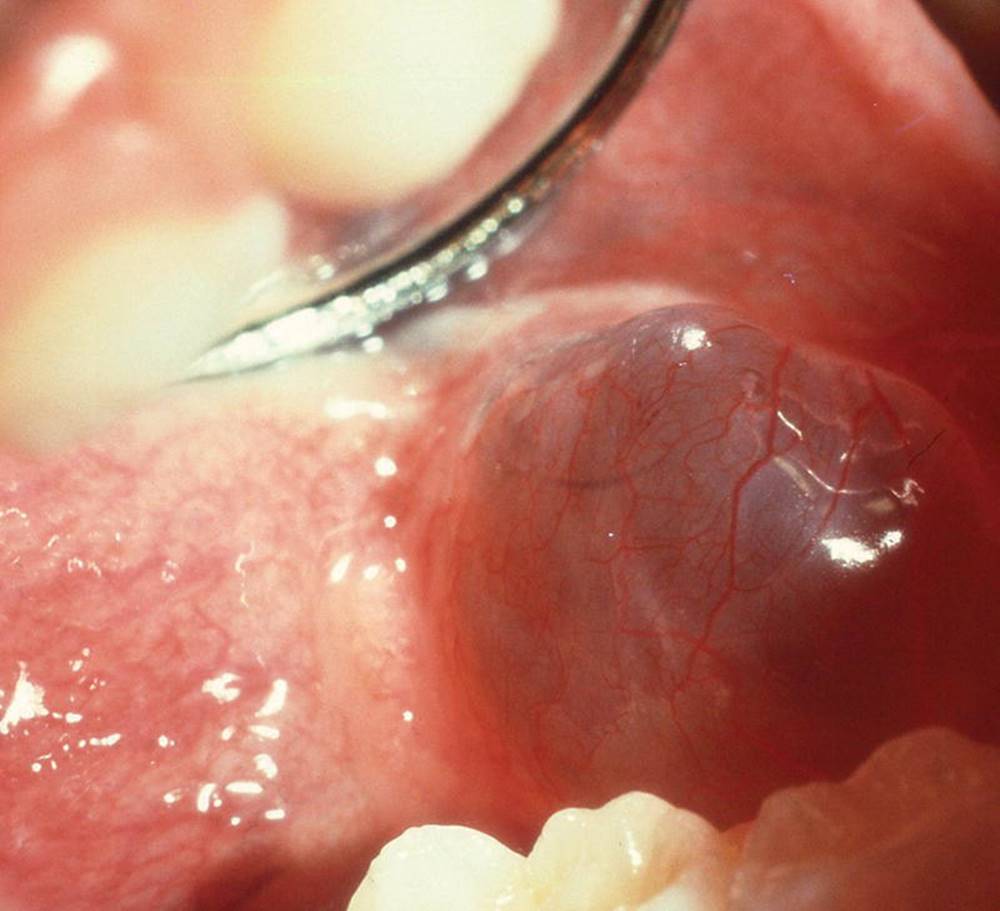

Ranula is essentially a large mucocele, located as a bluish swelling of the floor of the mouth (Figure 15.18). It arises from the salivary glands in that region. Due to extravasation or retention of mucus from excretory ducts of sublingual glands caused by trauma or infection, the extensive translucent swelling may occur.

Figure 15.18 Ranula located in the floor of the mouth.